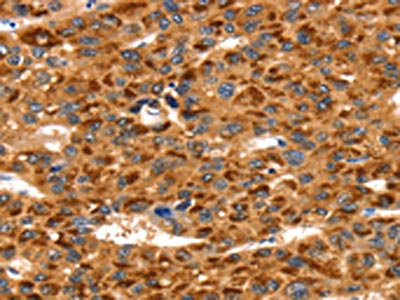

The image on the left is immunohistochemistry of paraffin-embedded Human liver cancer tissue using CSB-PA238975(TLN1 Antibody) at dilution 1/35, on the right is treated with synthetic peptide. (Original magnification: ×200)

The image on the left is immunohistochemistry of paraffin-embedded Human breast cancer tissue using CSB-PA238975(TLN1 Antibody) at dilution 1/35, on the right is treated with synthetic peptide. (Original magnification: ×200)